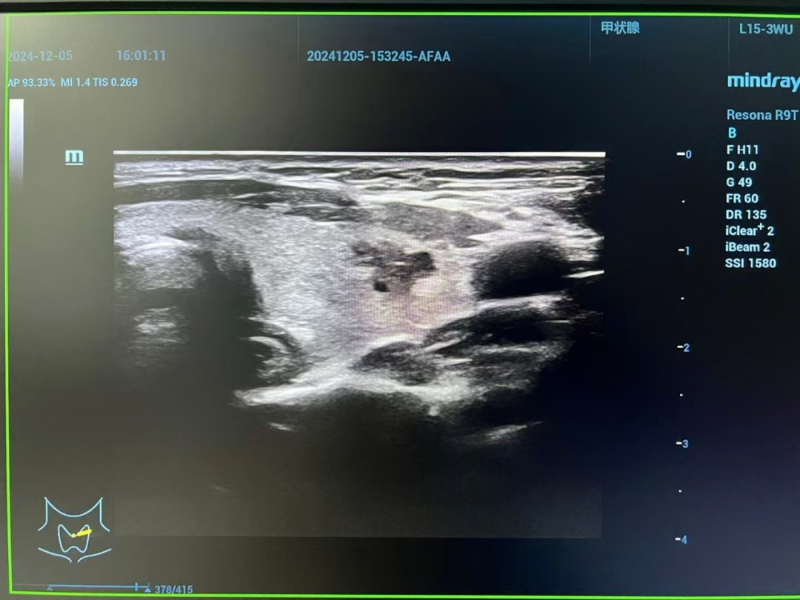

△術前評估

術前評估階段,專家團隊啟用高分辨率頸部超聲與先進磁共振成像技術,全方位、多維度掃描剖析。影像數據精準揭示:李女士左側甲狀腺結節小于1厘米,其包膜間距超2毫米,周邊組織未現侵襲跡象,淋巴結轉移亦無跡可尋。經嚴格篩選,甲狀腺微小乳頭狀癌微波消融手術指征確鑿無疑,為后續精準施治筑牢根基。